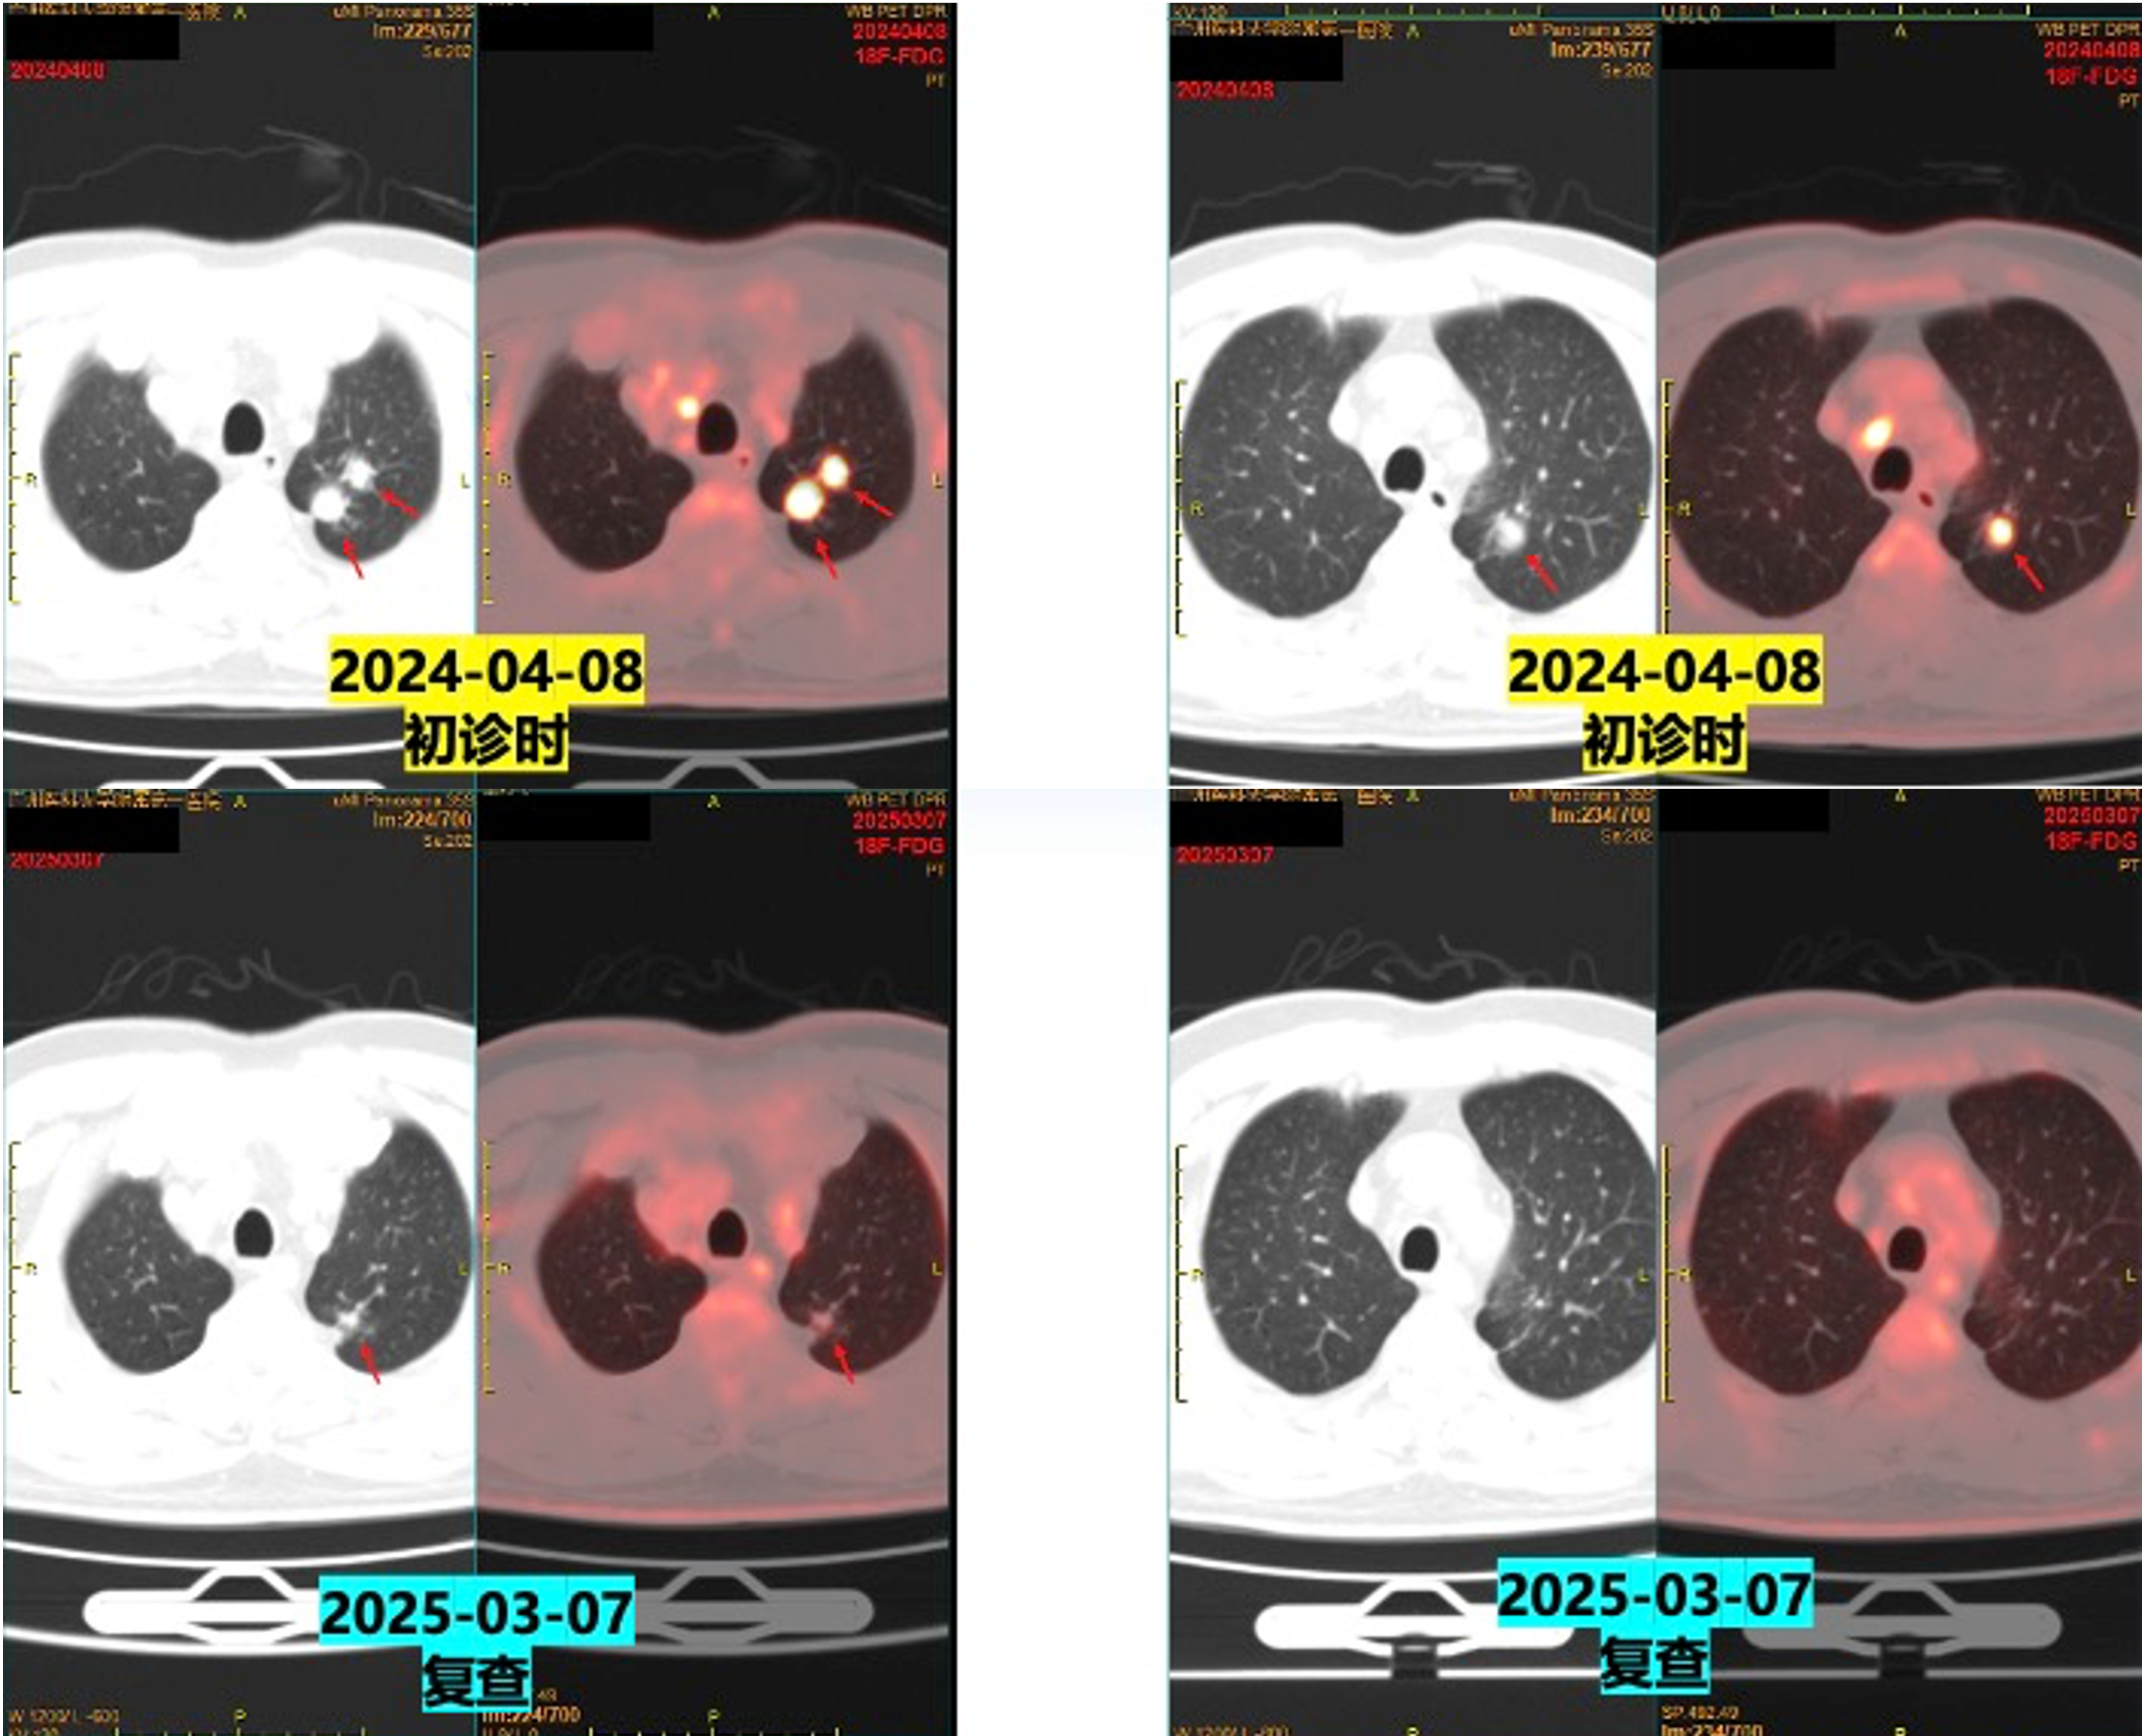

2024-04-08(初诊)vs 2025-03-07(复查)PET/CT:

左肺上叶尖后段实性结节体积缩小(较大约0.8×0.8×1.1cm vs 原1.9×1.8×2.4cm);

左肺门、纵隔多发淋巴结转移瘤体积缩小;

左侧肾上腺结合部增粗程度减轻。

在2025年3月7日复查petCT后,建议患者行原发病灶或者肺门、纵隔淋巴结的放疗,但是患者家属自觉目前治疗疗效理想,患者体能状态良好,暂不愿意行放疗。

疗效评估:PR(部分缓解)。